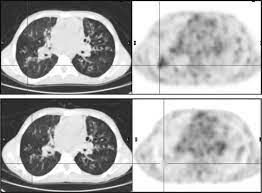

Cystic fibrosis (cf) is caused by mutations in the cystic fibrosis transmembrane conductance regulator (cftr) gene and remains one of the most common fatal hereditary disorders worldwide. Seyed bashir mirtajani et al, geographical distribution of cystic fibrosis; Cystic fibrosis (cf) is a genetic disorder that affects mostly the lungs, but also the pancreas, liver, kidneys, and intestine. Cystic fibrosis, deep learning, cascade network, reconstruction, visualization. Care guidelines for nutrition management.

Pulmonology Abstract Europe Pmc from europepmc.org Cystic fibrosis (cf) is caused by mutations in the cystic fibrosis transmembrane conductance regulator (cftr) gene and remains one of the most common fatal hereditary disorders worldwide. Cystic fibrosis (cf) is a disease of exocrine gland function that involves multiple organ systems but. Collins ct, gibson ra, anderson pj, et al. This is partly because the lungs are often severely affected and the cause of significant morbidity and mortality. Transurethral resection of the prostate. Cystic fibrosis is an autosomal recessive disorder, and most carriers of the gene are asymptomatic. Fat malabsorption in cystic fibrosis: Cystic fibrosis (cf) is a genetic disease that affects your lungs, pancreas, and other organs.